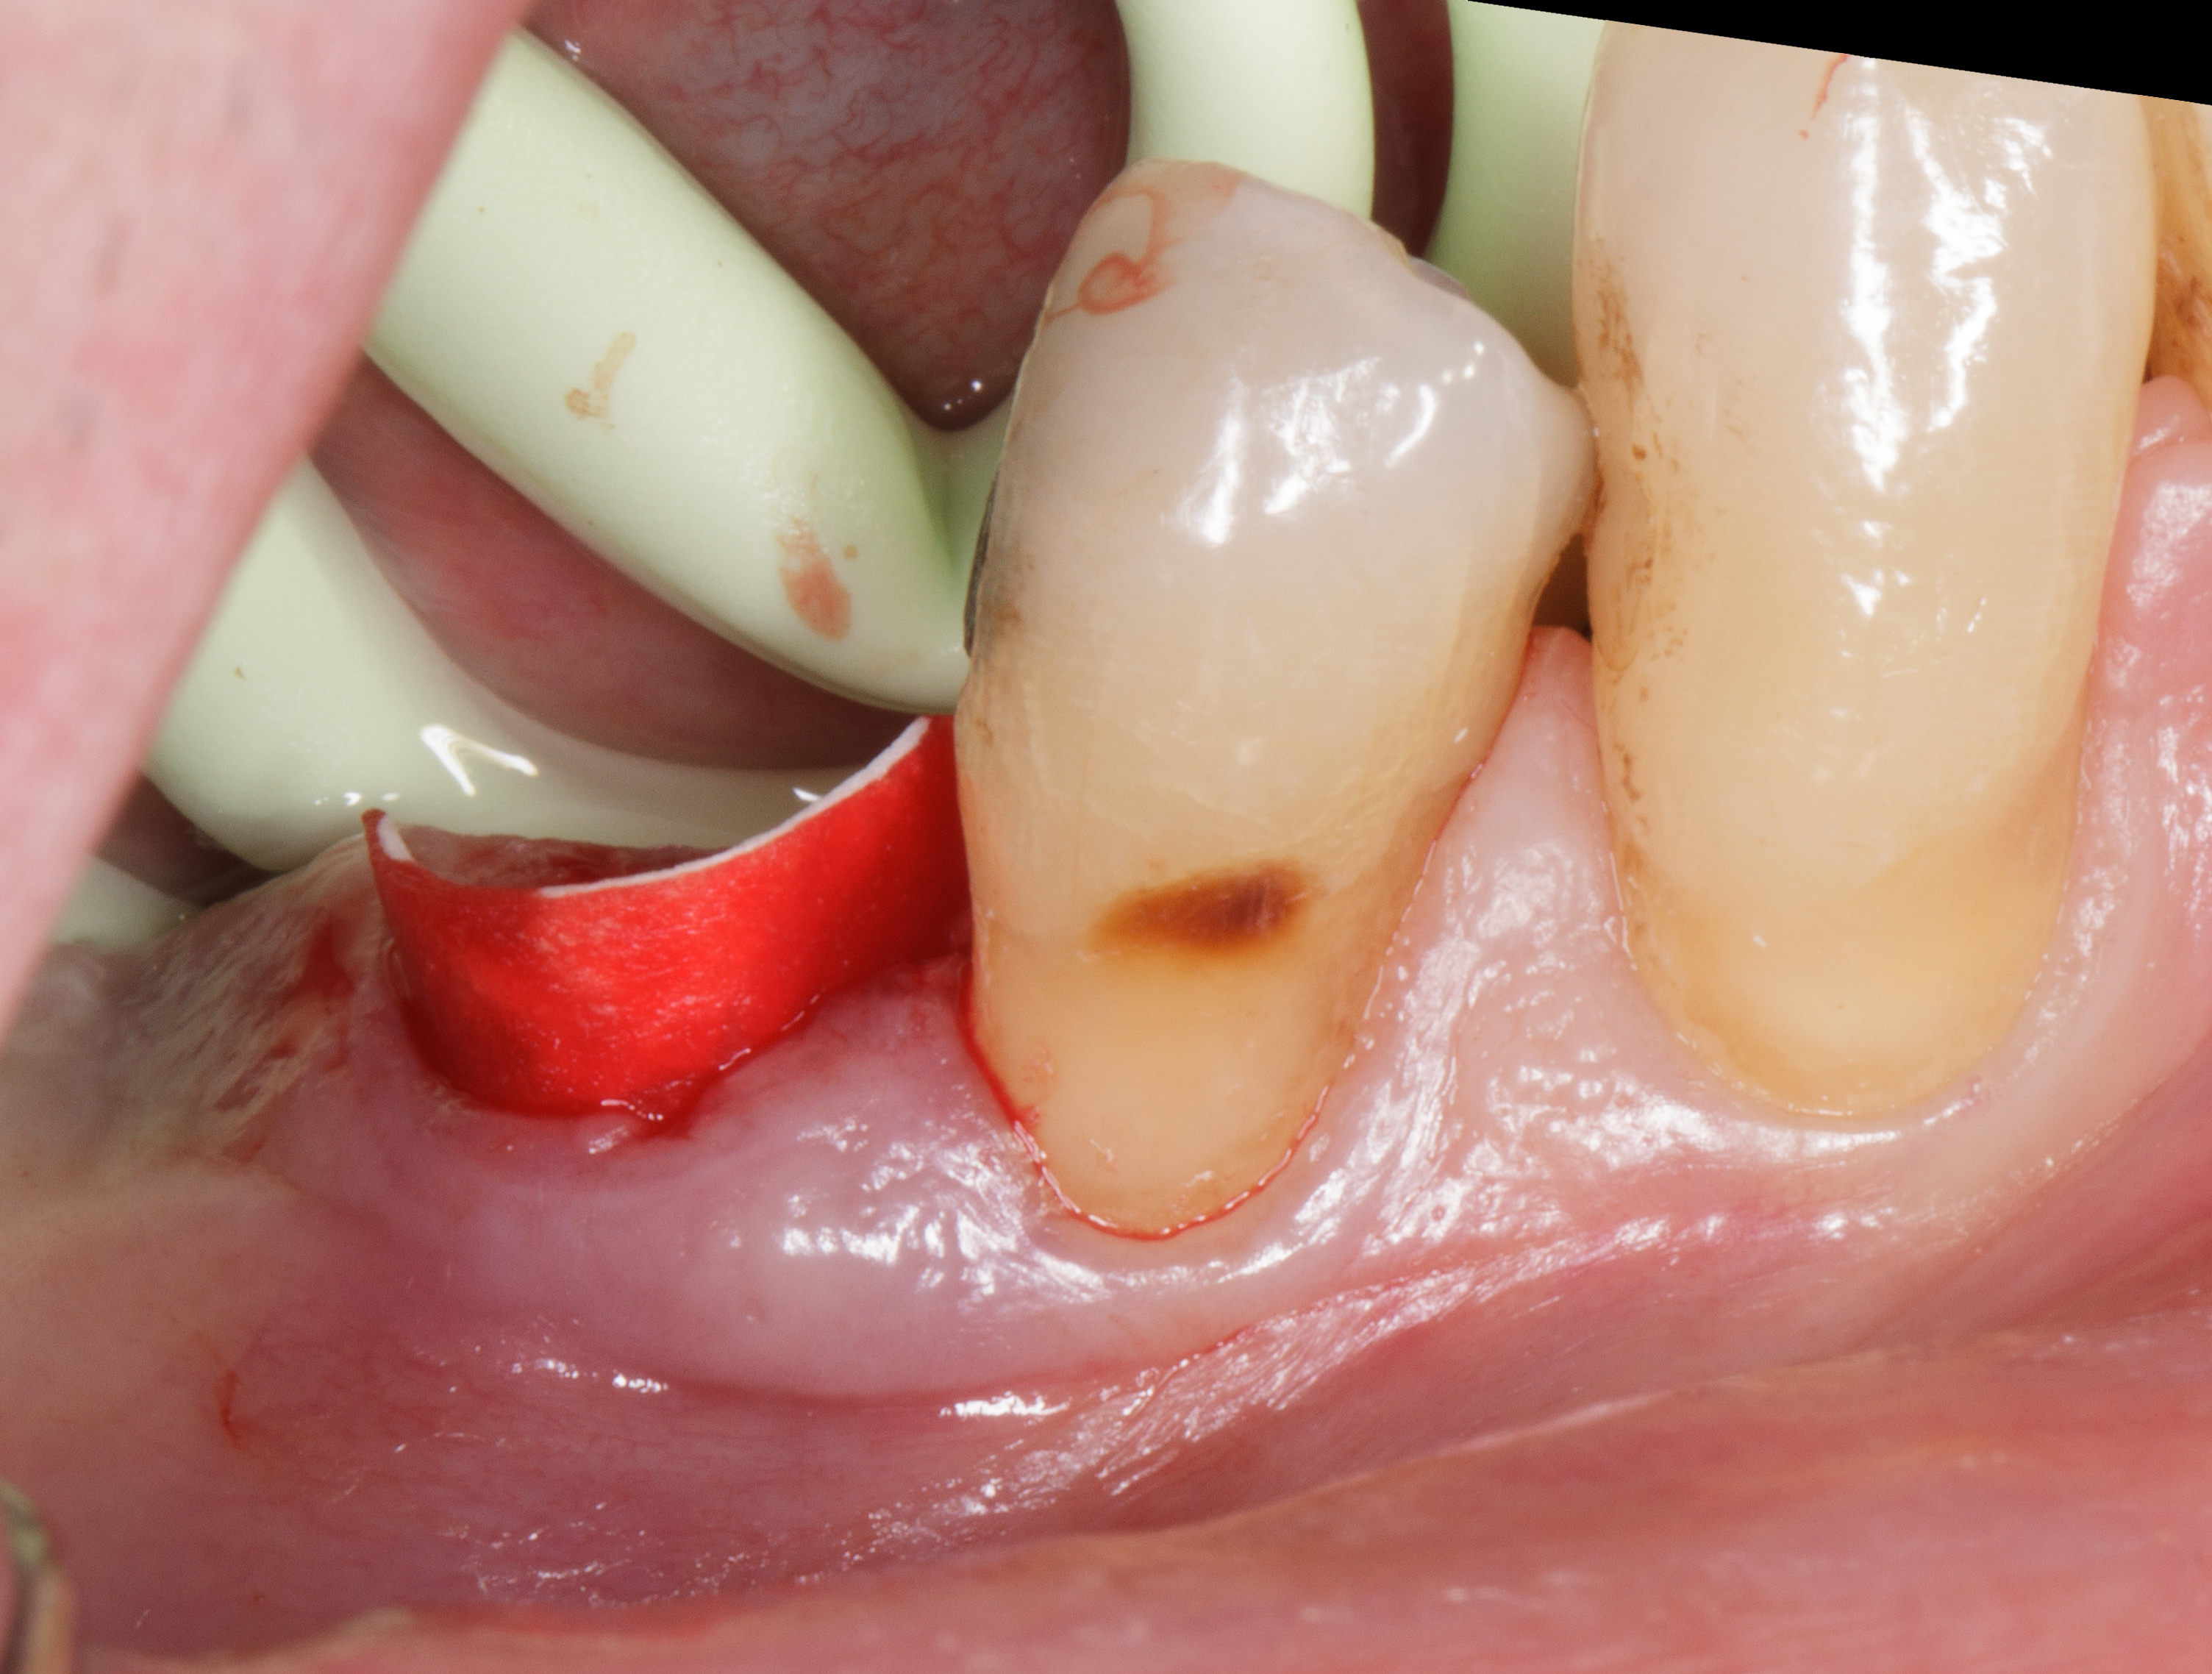

Riempimento dell’alveolo post-estrattivo: inserimento di granuli di particolato osseo per riempire in modo omogeneo l’alveolo post-estrattivo fino al livello della cresta ossea residua22, 23. Il particolato osseo viene idratato con soluzione salina almeno 15 minuti prima dell’inserimento nell’alveolo. Due, tre minuti prima dell’inserimento nella cavità, alcune gocce di sangue del paziente vengono aggiunte al particolato osseo per impregnare i granuli (prima fase, riempimento dell’alveolo post-estrattivo: FILL).

Sigillatura dell’alveolo post-estrattivo: sigillatura dell’alveolo con due strati di NeoGen® Collagen Firm, sagomati per adattarsi alla forma dell’alveolo e sovrapposti uno sull’altro per coprire perfettamente l’innesto osseo sottostante (Figura 9).

La completa sigillatura dell’alveolo viene perfezionata mediante la sutura Hidden X24 dei bordi gengivali dell’alveolo in modo che si introflettano sulla membrana dermica.

Coronalmente alla Firm viene inserita una medicazione al collagene Neogen Foam a protezione del sigillo dermico (seconda fase, sigillatura dell’alveolo post-estrattivo: SEAL) (Figure 10-11).

Dopo la rimozione della sutura normalmente si procede con un piano di mantenimento parodontale e di controllo sino a completa integrazione del graft osseo, ma il paziente, a soli 25 giorni dall’intervento di preservazione alveolare in posizione 4.5, richiede l’inserimento di un impianto in posizione 4.6.

Questa situazione, anche se non prevista dal piano di trattamento iniziale, consente di valutare clinicamente a cielo aperto il pattern di guarigione ossea e connettivale nel primo mese dopo l’intervento rigenerativo post-estrattivo (Figura 12).

Dopo aver inciso un lembo mucoperiosteo senza incisioni di scarico verticali, si vede la zona oggetto di estrazione omogeneamente riempita da tessuto osteoide in fase di maturazione.

Una gran parte della membrana riassorbibile posta all’interno dell’alveolo è ancora ben evidente e adesa al tessuto in fase di maturazione.